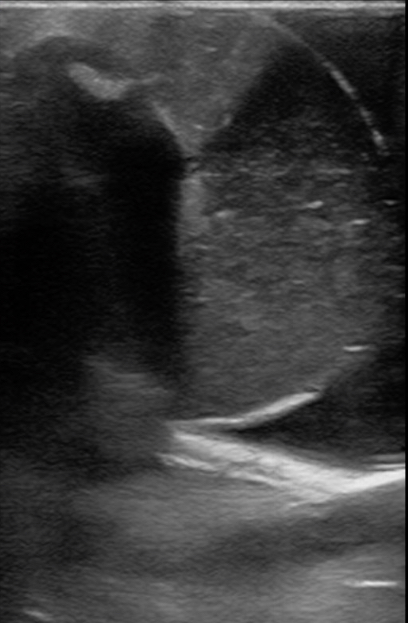

Figure 11. A model with normal testicle and a hydrocele.

Figure 12. A model with normal testicle, epididymis in view, and a hydrocele.